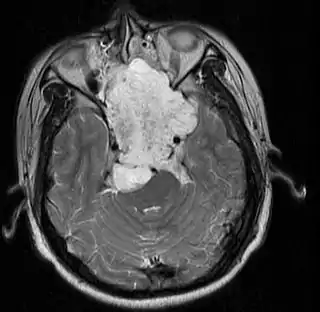

![]() Imagen de RMN de un cordoma en un varón de 17 años, vista axial. | ||